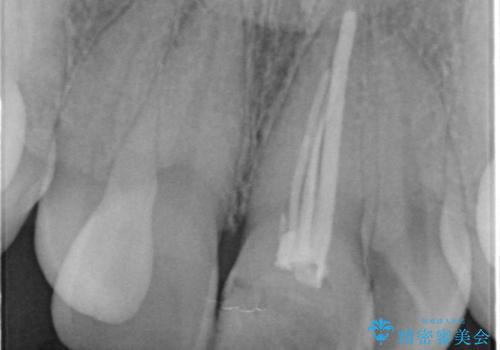

- 前歯の見た目が気になるとの事で来院。

根の治療のやりかえは希望されなかったので土台だけやりかえを行い、ジルコニアクラウンで治療を行いました。

- ジルコニアクラウンスタンダード・仮歯・ファイバーコア 18.7万円費用は治療当時の料金となります